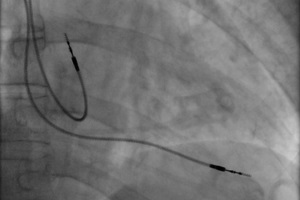

Принципиально новое решение оперативного лечения стенозирующих осложнений при атеросклерозе предложили в 1964 г. C.T. Dotter и M.P. Judkins.